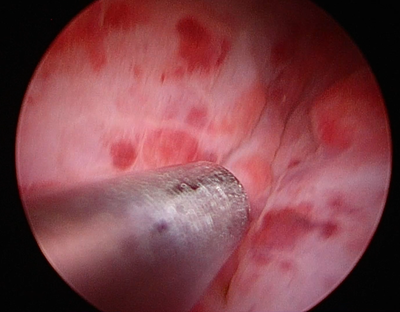

お腹に5-10mm程度の小さな穴をあけてそこから腹腔鏡をお腹の中に挿入します。まずは内視鏡で膀胱を確認してお腹に引っ張ってきてお腹の壁に少し固定します。その小さな傷から膀胱を小切開し、カメラを膀胱内に入れていき内部を観察します。膀胱に開けた穴からカメラや鉗子と呼ばれる器具を入れて膀胱の中で手術をしたり、吸引管と呼ばれる液体を吸い取るための管状の器具をいれます。内視鏡カメラは非常に大きく拡大して内部を観察するために小さな結石や結晶、傷やポリープなどの細かな観察が得意です。

結石の摘出

カメラで確認した結石は吸引もしく鉗子による除去を行います。数㎜の小さな結石や結晶は吸引管とよばれる液体を吸引する器具を用いて除去を行います。先端が3-5mm程度ですのでこれ以下の結石はこの器具を用いて摘出します。イメージとしては掃除機を使って小さなホコリを吸い取ってしまような形になります。

5㎜以上など吸引が出来ない結石は鉗子と呼ばれる器具で実際に掴んで体外へ牽引します。この場合には一度に一つしか掴むことが出来ないために一つずつ摘出することになります。